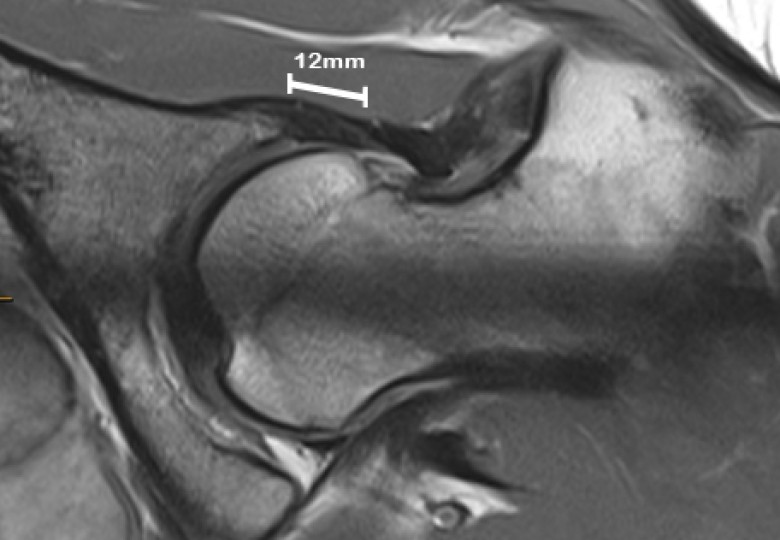

• Increased acetabular anteversion (a measure of the angle of the hip socket) and decreased lateral centre edge angle (LCEA, a measure of hip socket coverage) were associated with microinstability.